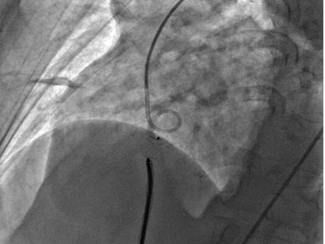

Postinfarct (PI) ventricular septal defect (VSD) usually occurs 2-7 days after untreated acute myocardial infarction (MI) due to interventricular septal rupture after necrosis. In the current era of primary percutaneous coronary intervention...